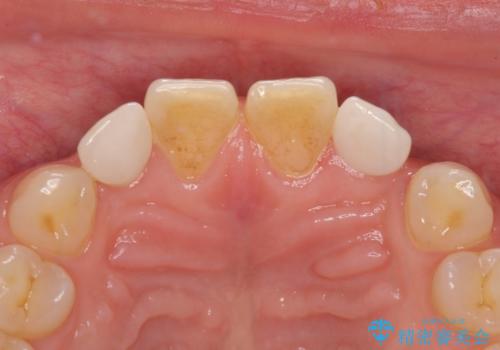

- 前歯の矮小歯に貼り付けられていたラミネートベニアが外れてしまったとのことで来院された患者様です。

反対側の矮小歯は裏打ちが金属であったため、両方の歯ともにオールセラミッククラウンにて補綴することとしました。

前歯の隙間や、周りの歯と色合いの違いなどはあまり気にしていらっしゃらなかったため、矮小歯の2歯を自然な大きさに仕上げました。

とても自然な歯が装着されたとのことで、患者様には大変満足していただきました。